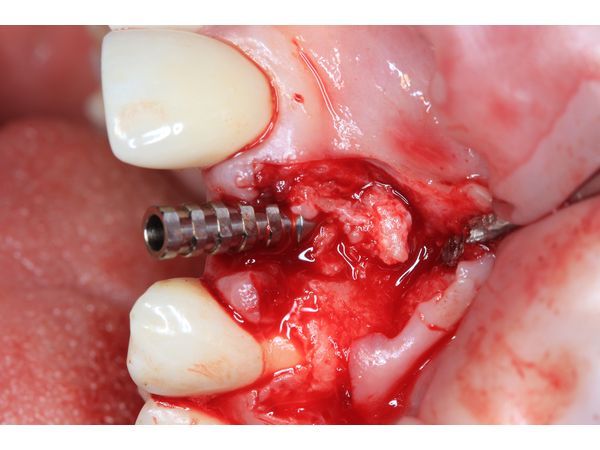

Пациентке сделали анестезию и сформировали микрохирургический доступ для удаления зуба и установки дентального импланта в оптимальную ортопедическую позицию. В зоне дефекта одна треть импланта осталась обнажённой.

Отсутствующую кортикальную пластинку реконструировали с помощью тройного трансплантата из зоны бугра верхней челюсти (забор произвели на стороне вмешательства). Чтобы зафиксировать трансплантат, его утрамбовали в зону дефекта.